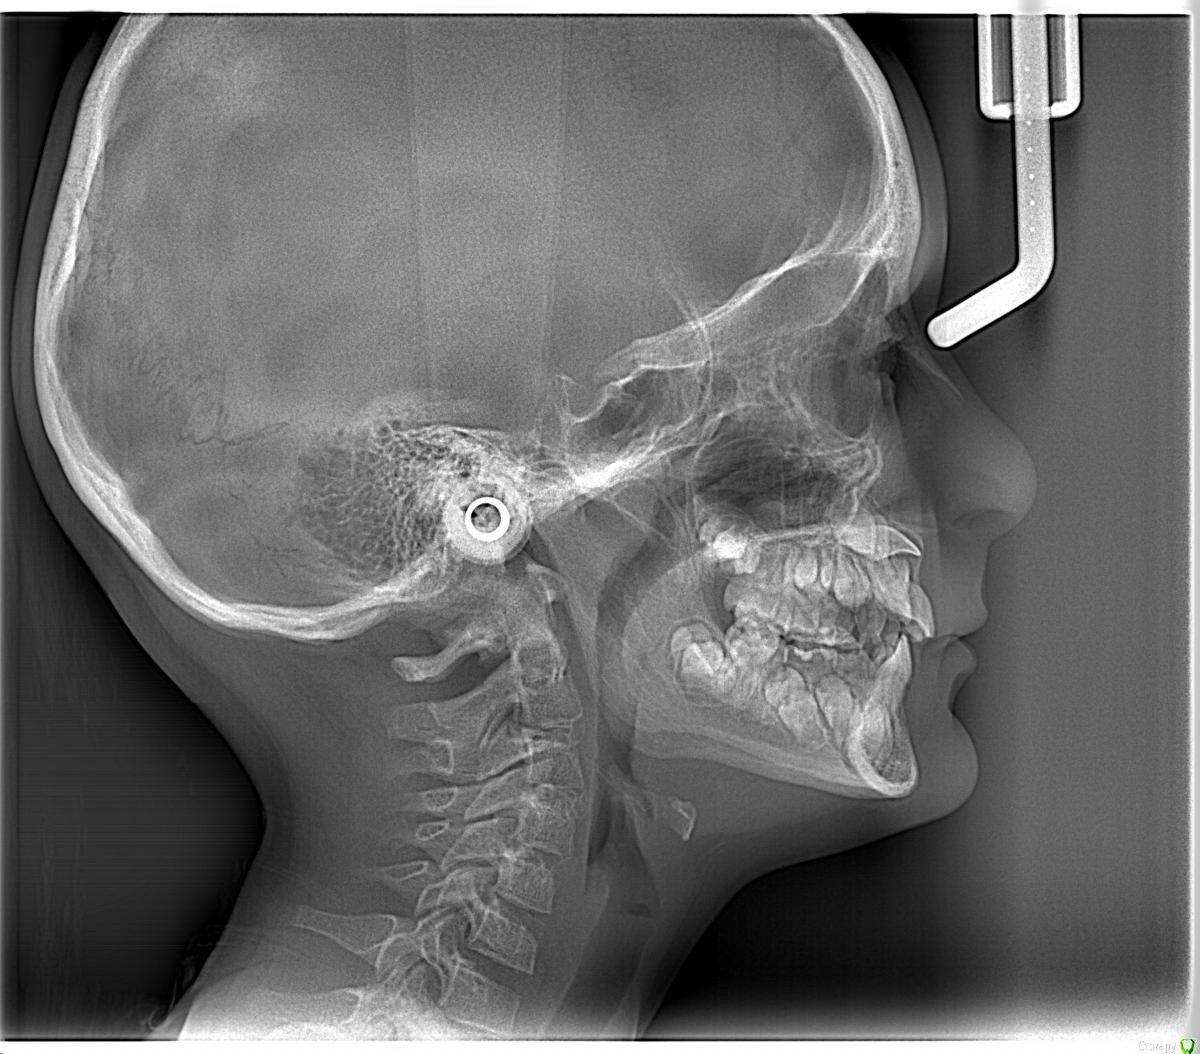

Opdihatop Опубликовано 9 января, 2017 Поделиться Опубликовано 9 января, 2017 Здравствуйте, коллеги! Хотел бы узнать ваше мнение по пациентке. Девочке 7 лет. План лечения в общем мне ясен и понятен. Меня интересует вопрос, когда лучше в данном случае убирать сверхкомплектный премоляр в области 21 зуба, потому что он начал двигать ц.л. вправо. Заранее спасибо! Ссылка на комментарий

Dok22 Опубликовано 11 января, 2017 Поделиться Опубликовано 11 января, 2017 Это не премоляр просто так виден 2-х мерный срез нужно КТ его грамотная интерпретация и хороший хирург.Сверхкомплектный удалять надо он блокирует 21 и 22. Ссылка на комментарий

Yana guapa Опубликовано 13 января, 2017 Поделиться Опубликовано 13 января, 2017 убрать молочный ц. резец. подождать 6-8 месяцев хотя бы (лучше год) - все ростковые зоны уже значительно выше будут, хирург не задет уже.сделать КТ. и удалить сверхкомплектный. Дать возможность опуститься ц. резцу.сильно долго ждать (до полного формирования корней) не вижу смысла. Очень похожа ситуация была у моей девочки (такое же расположение). - очень долго не хотел ц. резец спускаться. Райц-терапия в помощь)) вышел)) Ссылка на комментарий